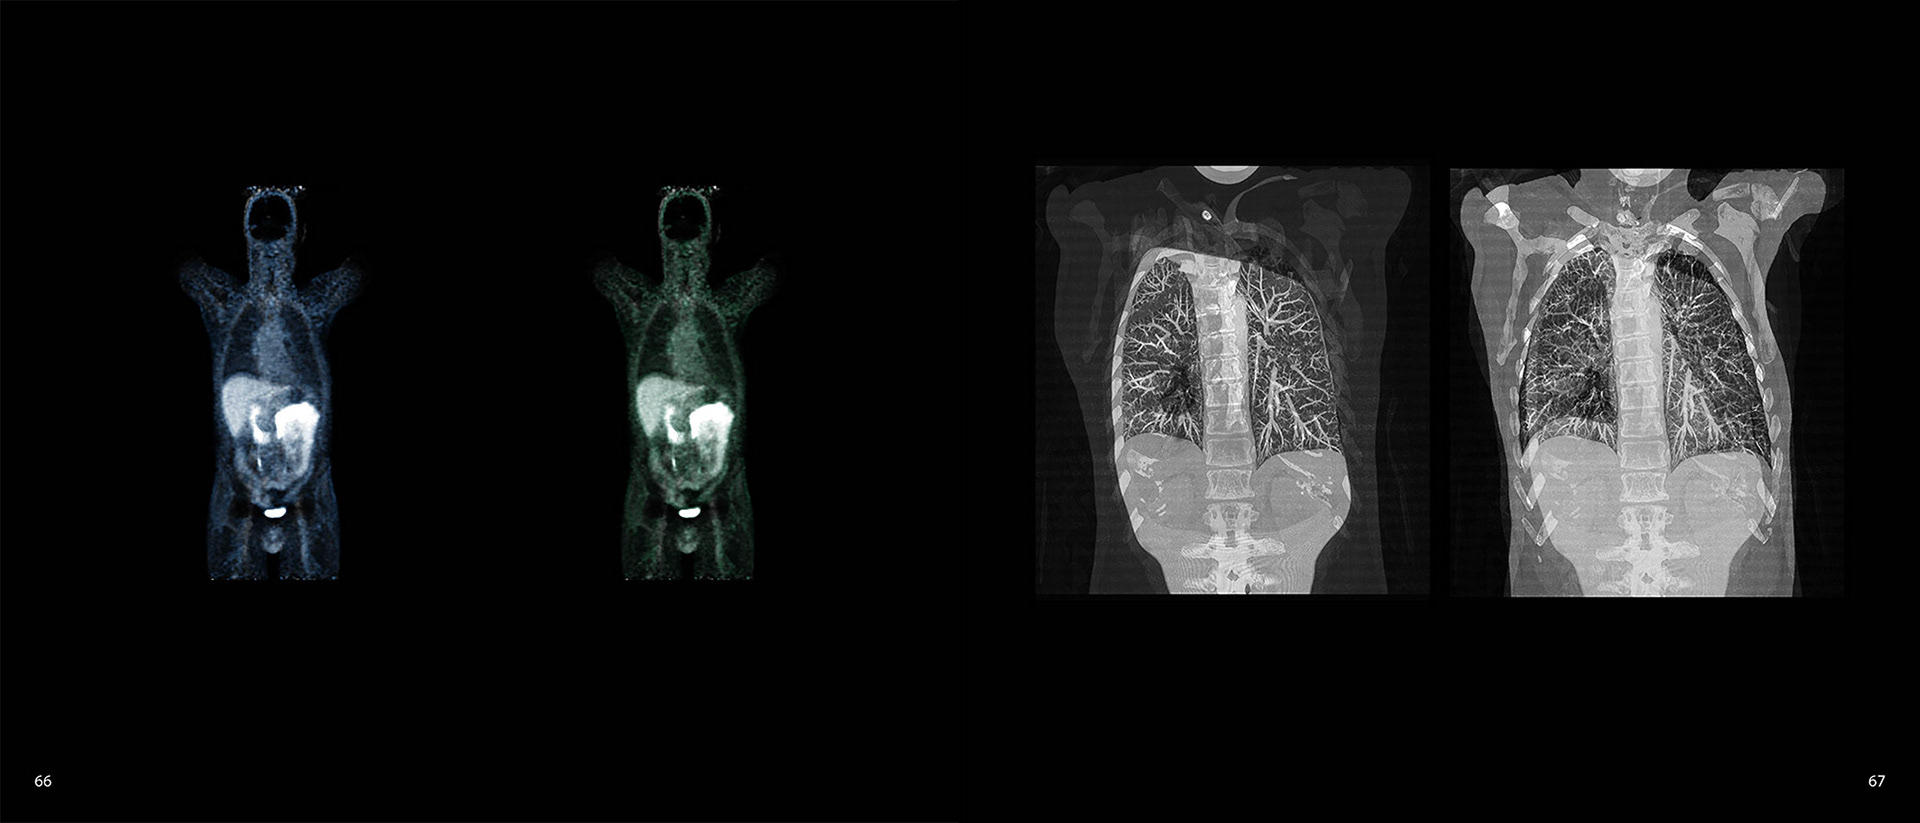

- medical scans, conducted in October and November 2015, to confirm the diagnois of prostate cancer, and to check for metastasising cancers elsewhere,